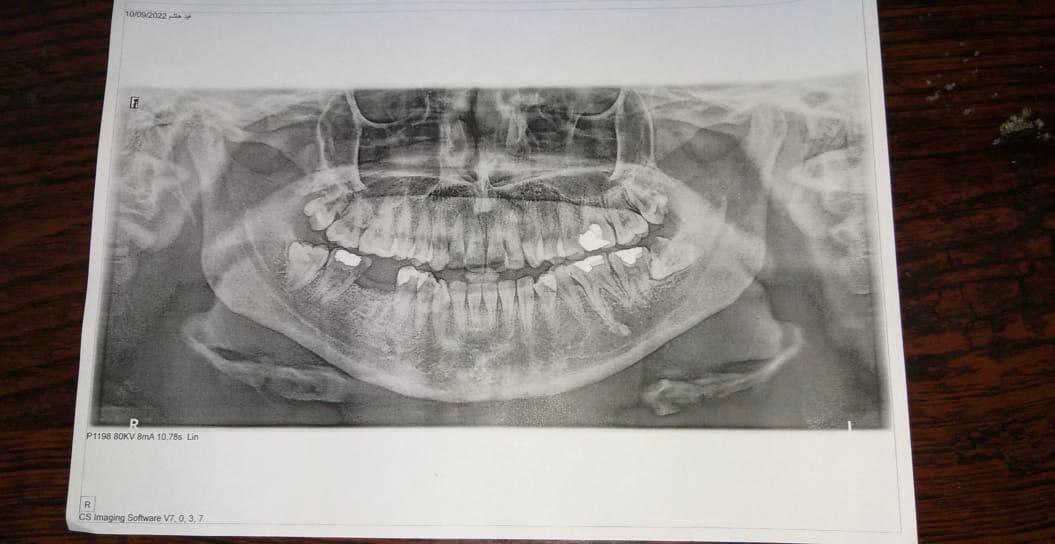

Performing surgical extractions in a dental surgery clinic